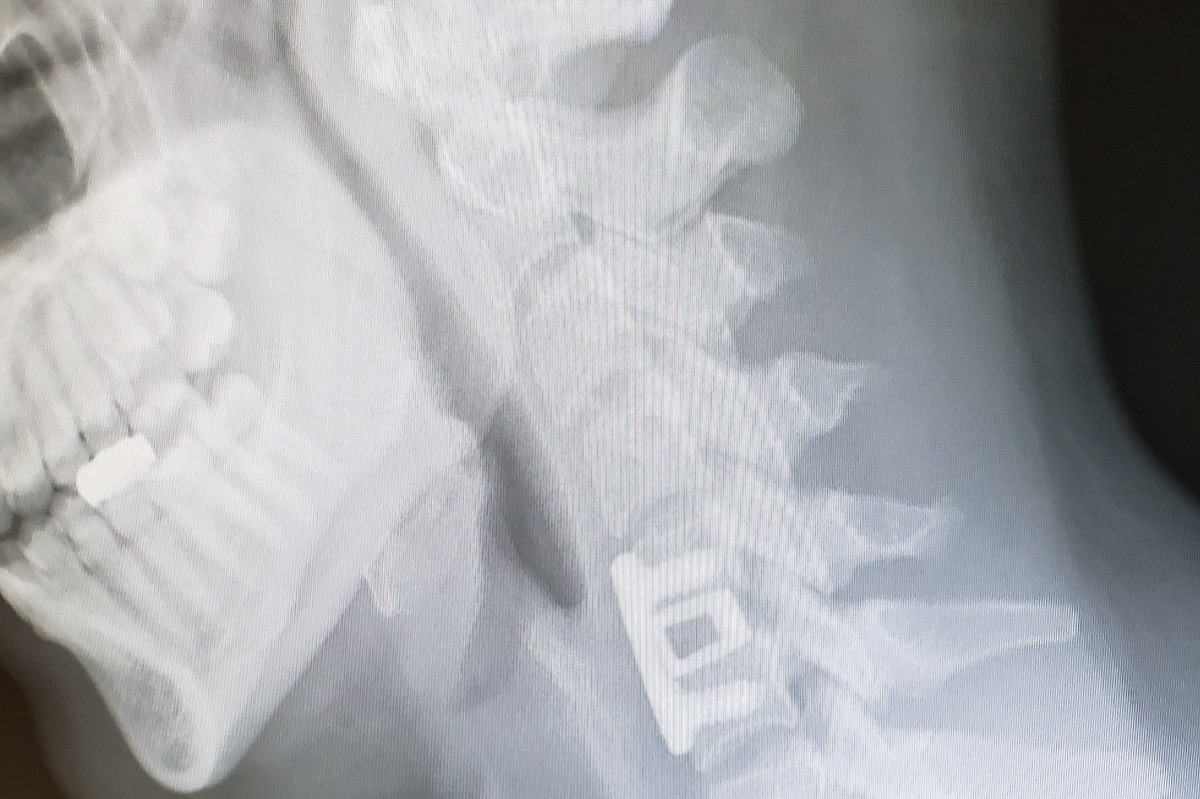

My CT scan taken on June of 2019,  ACDF pictured.